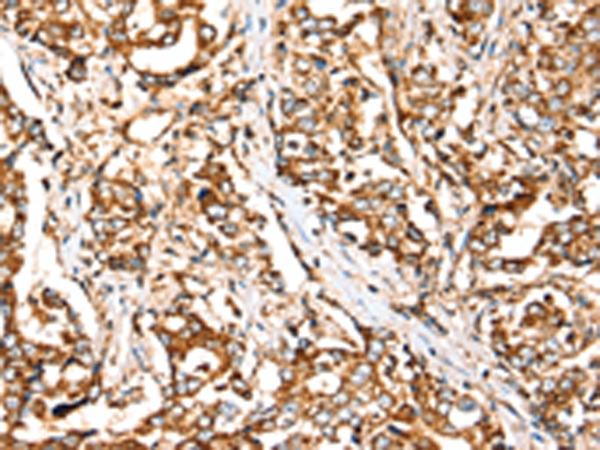

分类: 科研抗体货号: P12199别名: CRT; CT1; CRTR; CTR5; CCDS1应用: IHC反应种属: Human, Mouse, Rat